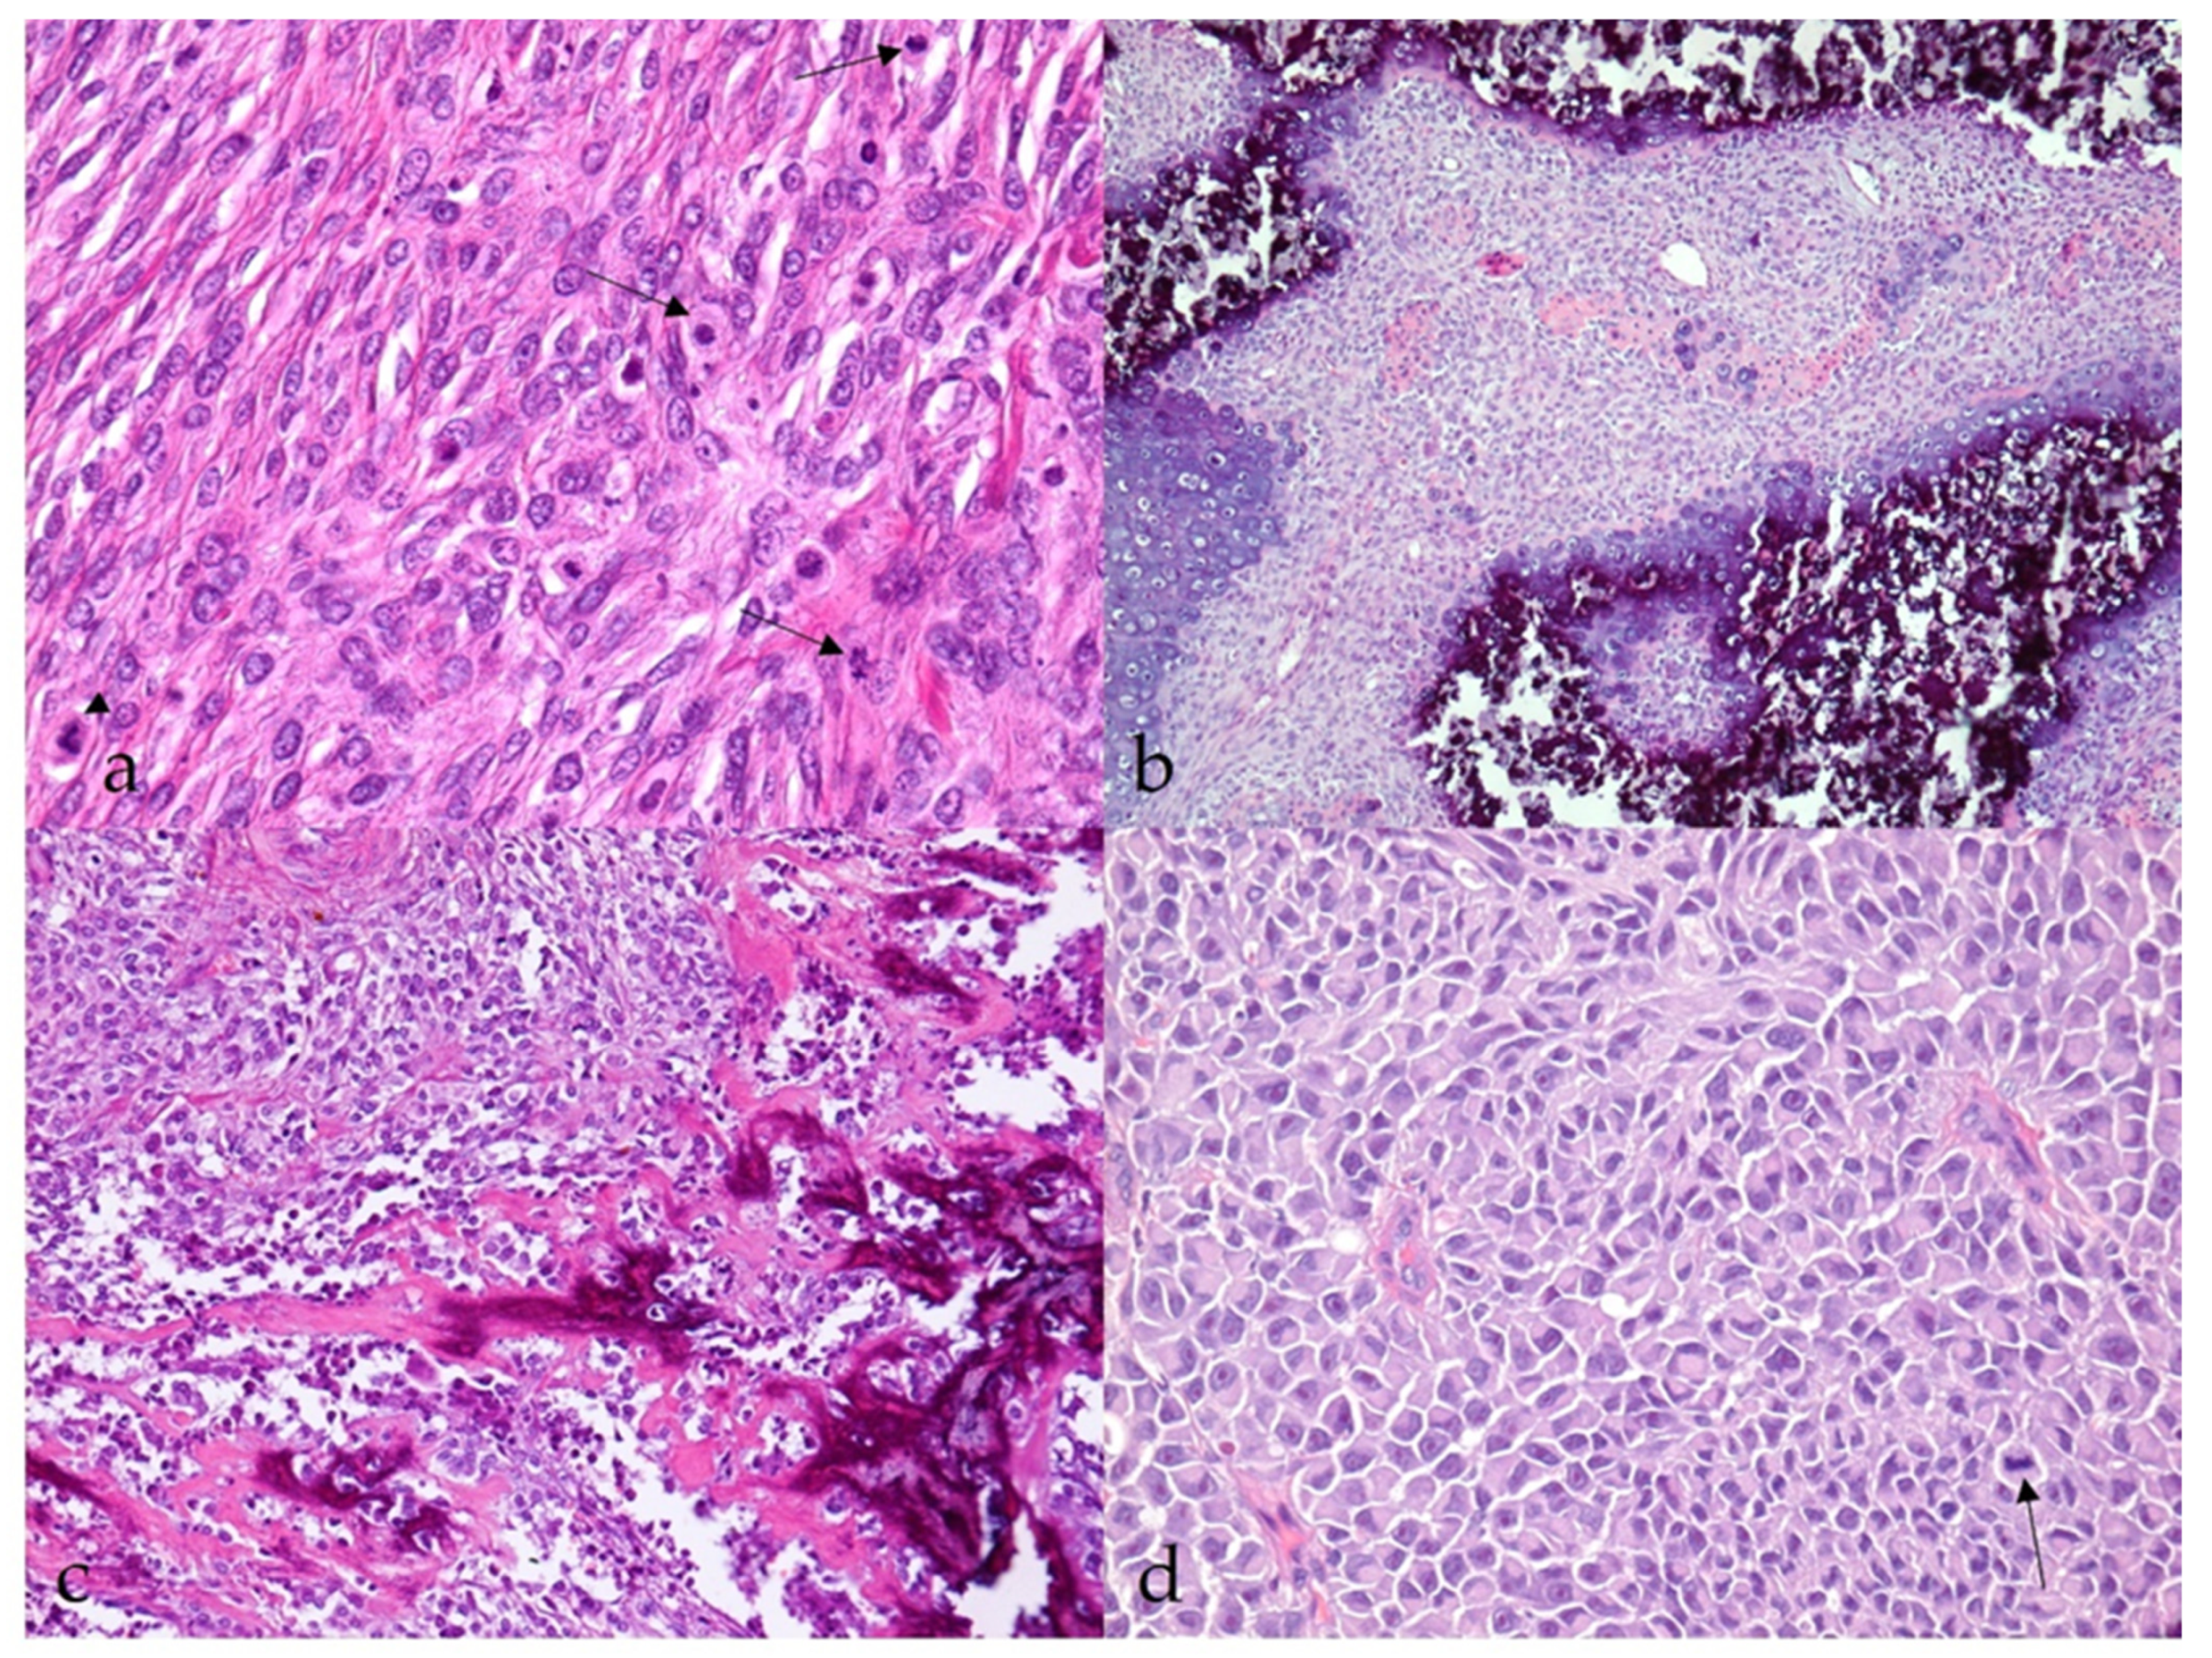

3.2.1. Benign Nerve Sheath Tumors

3.2.2. Malignant Nerve Sheath Tumors